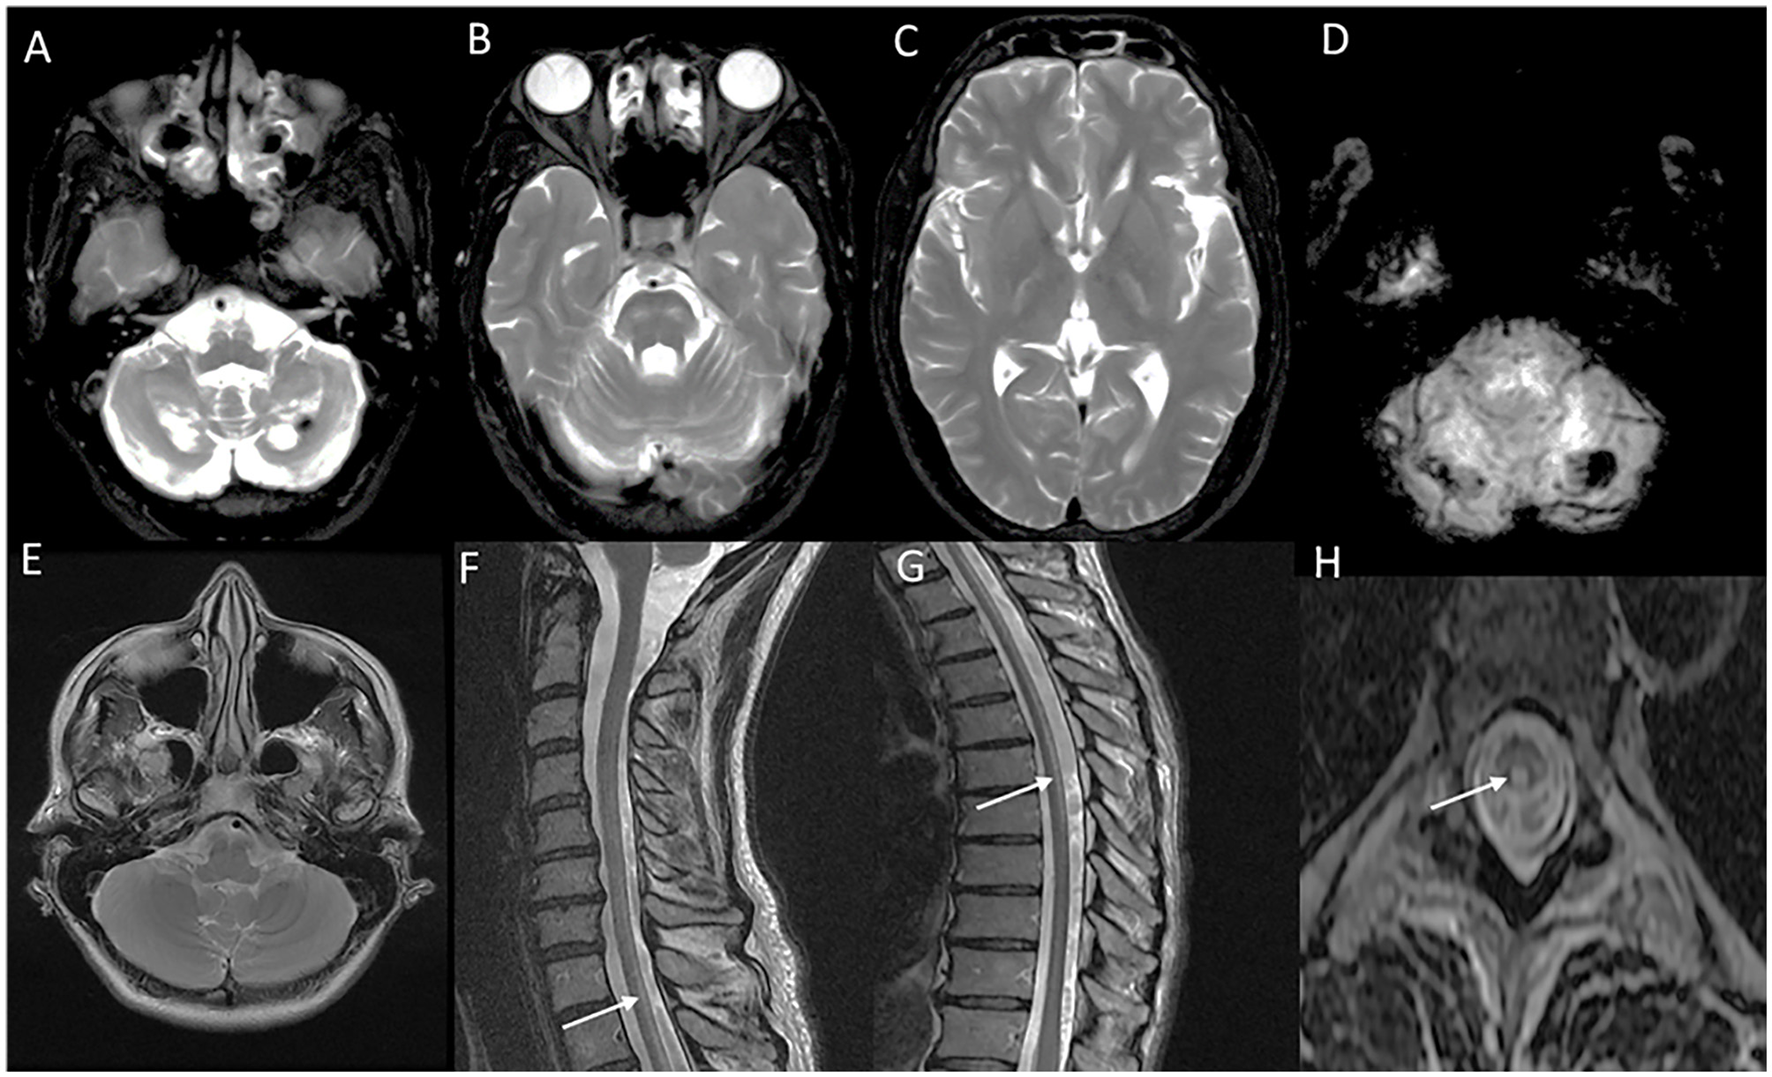

MRI brain findings are characterized by symmetric white matter hyperintensities in subcortical, deep, and periventricular white matter in frontal and parietal regions along with volume loss and ventricular dilatation (13, 73). Involvement of the external capsule, splenium, para-vermian region, and middle cerebellar peduncle is commonly seen (Figure 8). Involvement of these structures along with curvilinear DWI hyperintense lesions along the corticomedullary junction is probably a reliable imaging marker for the diagnosis of NIID (73). In the advanced stages, the corticomedullary DWI high-intensity signal appears to extend along the corticomedullary junction, but not into deep white matter (Figure 8). A small proportion of cases might lack diffusion changes. In acute encephalitic-like presentations, focal cortical hyperintensity and edema corresponding to the region of deficit are seen (13).

Figure 8

MRI brain findings in neuronal intranuclear inclusion disease (NIID). T2FLAIR sequences (A–D) reveal diffuse signal changes subcortical, periventricular, and deep white matter including splenium [arrow in (B)] and para-vermian region (A), along with corresponding DWI sequences (F–I) with high signal in a curvilinear pattern at the cortical gray–white matter junction of the supratentorial region. Imaging of a patient with NIID during recurrent encephalitis-like presentation revealing swelling, and signal changes involving right occipital gray matter in the T2FLAIR images (E) and abnormal leptomeningeal enhancement in the post-contrast sequence (J).